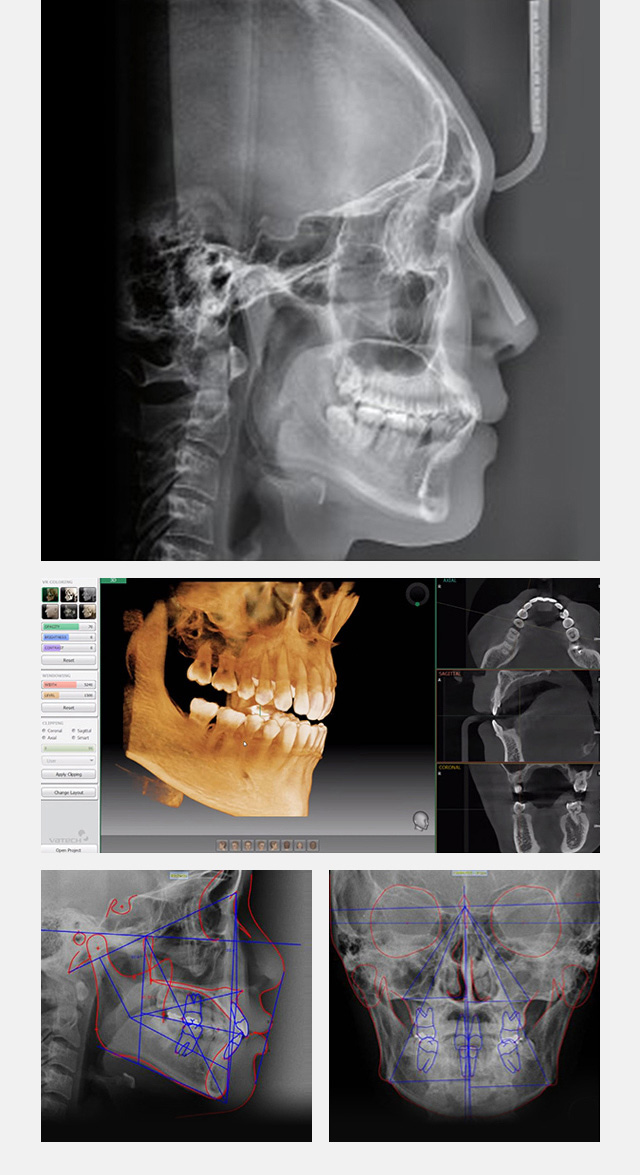

첨단장비로 얼굴형태와 치아형태를 분석해 다양한 케이스를 기반하여

첫 상담부터 대표원장의 상담으로 치료계획을 수립하며 마지막 스마일 라인까지 고려한

환자가 원하는 심미적인 미소라인을 찾아 드립니다.